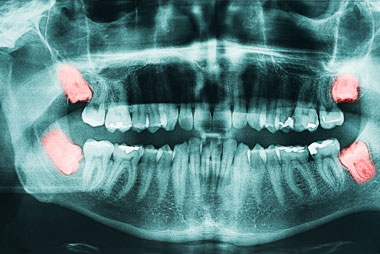

Warum sollten Sie Ihre Weisheitszähne im mittleren Alter oder später entfernen lassen?

Weisheitszähne sind ein Problem, das bekanntermaßen häufig bei Teenagern und Kindern auftritt. Was die meisten Menschen jedoch nicht wissen, ist, dass diese Erkrankung auch bei Menschen mittleren Alters zu Problemen führen kann.